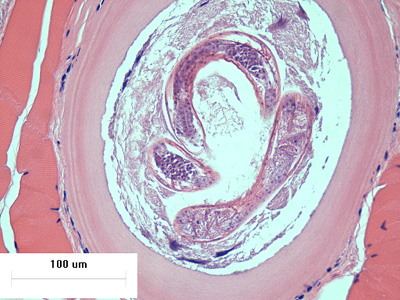

A hunter prepared dried jerky from fresh bear meat and provided some to a group of friends. Most developed moderate to severe abdominal pain, nausea, and fatigue within 48 hours. Some of the bear meat was submitted for laboratory testing. Images of stained histological sections of bear meat were sent to the DPDx Team for confirmation of parasites. Figures A and C were taken at 200x magnification; Figures B, D, and E were taken at 400x magnification. What is your diagnosis? Based on what criteria?

Figure A